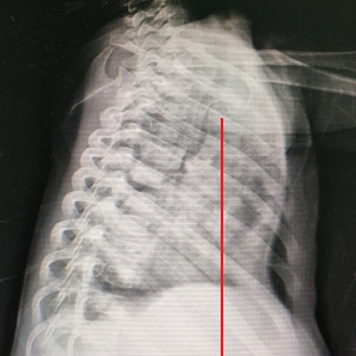

Shortly after birth, the child was diagnosed with pectus excavatum, manifested as a sunken anterior chest wall. This condition often causes breathing difficulties and even severe paradoxical breathing. Additionally, the child has suffered multiple episodes of severe pneumonia, leading to several hospitalizations without full recovery. Given the severity of the chest wall deformity and its complications, the parents are eager for early surgical treatment.

The mid-lower part of the anterior chest wall exhibits a noticeable depression, accompanied by significant paradoxical breathing. Moreover, heart pulsations in the anterior chest wall and a protruded costal arch are evident. The patient was diagnosed with severe pectus excavatum, which had caused significant compression of the heart and lungs.